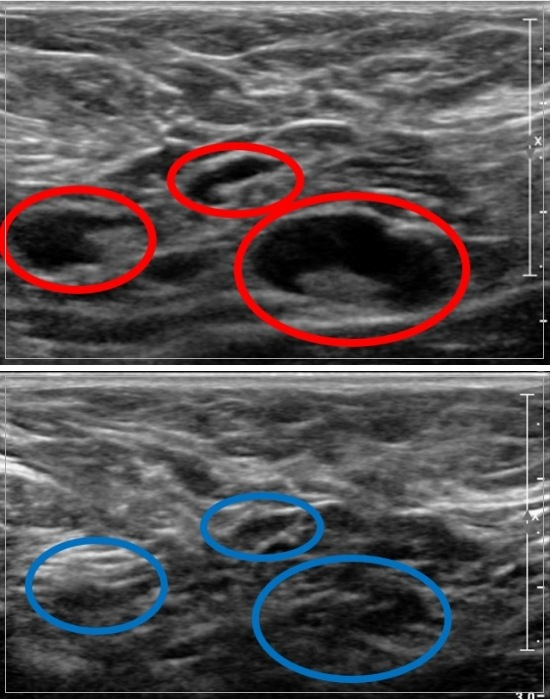

연구팀은 먼저 림프절병증의 악성도를 확인하는 기존 초음파검사 평가 방법으로 코로나19 백신 부작용으로 생긴 림프절병증의 특징을 분석했다. 림프절병증의 악성도를 평가하는 7가지 초음파검사 결과 특징인 ▲림프절 피질(겉층)의 최대 두께(4.5㎜ 미만 또는 이상) ▲림프절의 모양(타원형 또는 원형) ▲림프절 경계의 불규칙 정도 ▲비대칭적인 피질 비후(딱딱해지고 두꺼워짐) ▲림프절 일부인 지방문의 보존 여부 ▲부어오른 림프절의 개수 ▲부어오른 림프절의 위치 등을 적용해 분석했다.

이 결과 림프절 피질의 최대 두께와 비대칭적인 피질 비후 등 2가지가 악성 림프절병증의 초음파검사 결과와 유사했다. 특히 림프절 피질의 최대 두께에서 나타나는 악성 림프절병증과의 유사성은 코로나19 백신 접종 후 4주 이내에 초음파검사를 했거나 mRNA 계열의 화이자, 모더나 백신을 접종한 경우 더욱 높았다.

초기 연구에서 기존 초음파검사 평가 방법으로는 양성과 악성 림프절병증을 구별하기 어렵다는 점을 인지한 연구팀은 추가로 림프절병증의 악성도를 평가하는 7가지 초음파검사 결과 특징을 바탕으로, 코로나19 백신 부작용에 의한 림프절병증을 감별할 수 있는 새로운 림프절 이상 점수를 개발했다.

연구팀의 림프절 이상 점수는 7점 만점으로 점수가 낮을수록 양성 가능성이, 점수가 높을수록 악성 가능성이 높은 것으로 설계했다. 이를 113명의 양성 림프절병증 그룹에 적용한 결과, 평균 점수는 2.45점으로 낮아 실제 악성 림프절병증의 가능성이 떨어지는 것으로 확인됐다.